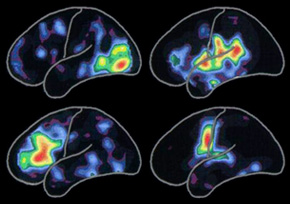

左圖所顯示的陽電子釋放 X 線斷層掃瞄(PET scan)顯示不同腦部活動的模式:

閱讀(左上)

聆聽詞語(右上)

思考詞語(左下)

說出詞語(右下)